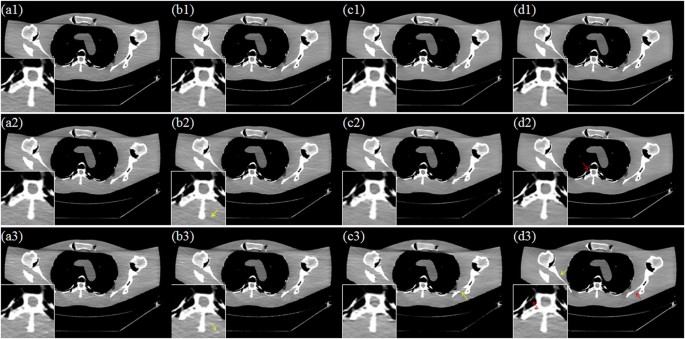

Figure 7 depicts the results from different reconstruction algorithms with three scanner protocols. From top to bottom, the scanner protocols are Case D1, Case D2 and Case D3, respectively. From left to right, the reconstruction algorithms are TV, PICCSDFR, GDSIR and DP-PICCS, respectively. We can observe that the smooth regions are plagued by some block and sharp artifacts, which may have resulted from the TV piecewise smooth constraint in TV and PICCSDFR methods results in Fig. 7(a3) and (b3). This is because the gradient variation based TV constraint fails to provide good discrimination ability between desirable tissue structure features and streak-artifacts. In the third columns in Fig. 7, the GDSIR method works well in suppressing noise and artifacts but at the cost of smoothing out some organ edges (see the zoomed region and yellow arrow in Fig. 7(c3)). Comparing the results in all the zoomed regions, we can see that the proposed DP-PICCS method achieves the best image quality in structure retention and noise-artifact suppression for all the three dose levels.

Selected axial views in the simulated phantom reconstruction. From left to right, images reconstructed using the TV, PICCSDFR, GDSIR and DP-PICCS methods from Case D1 (the first row), Case D2 (the second row) and Case D3 (the third row) projection, respectively.